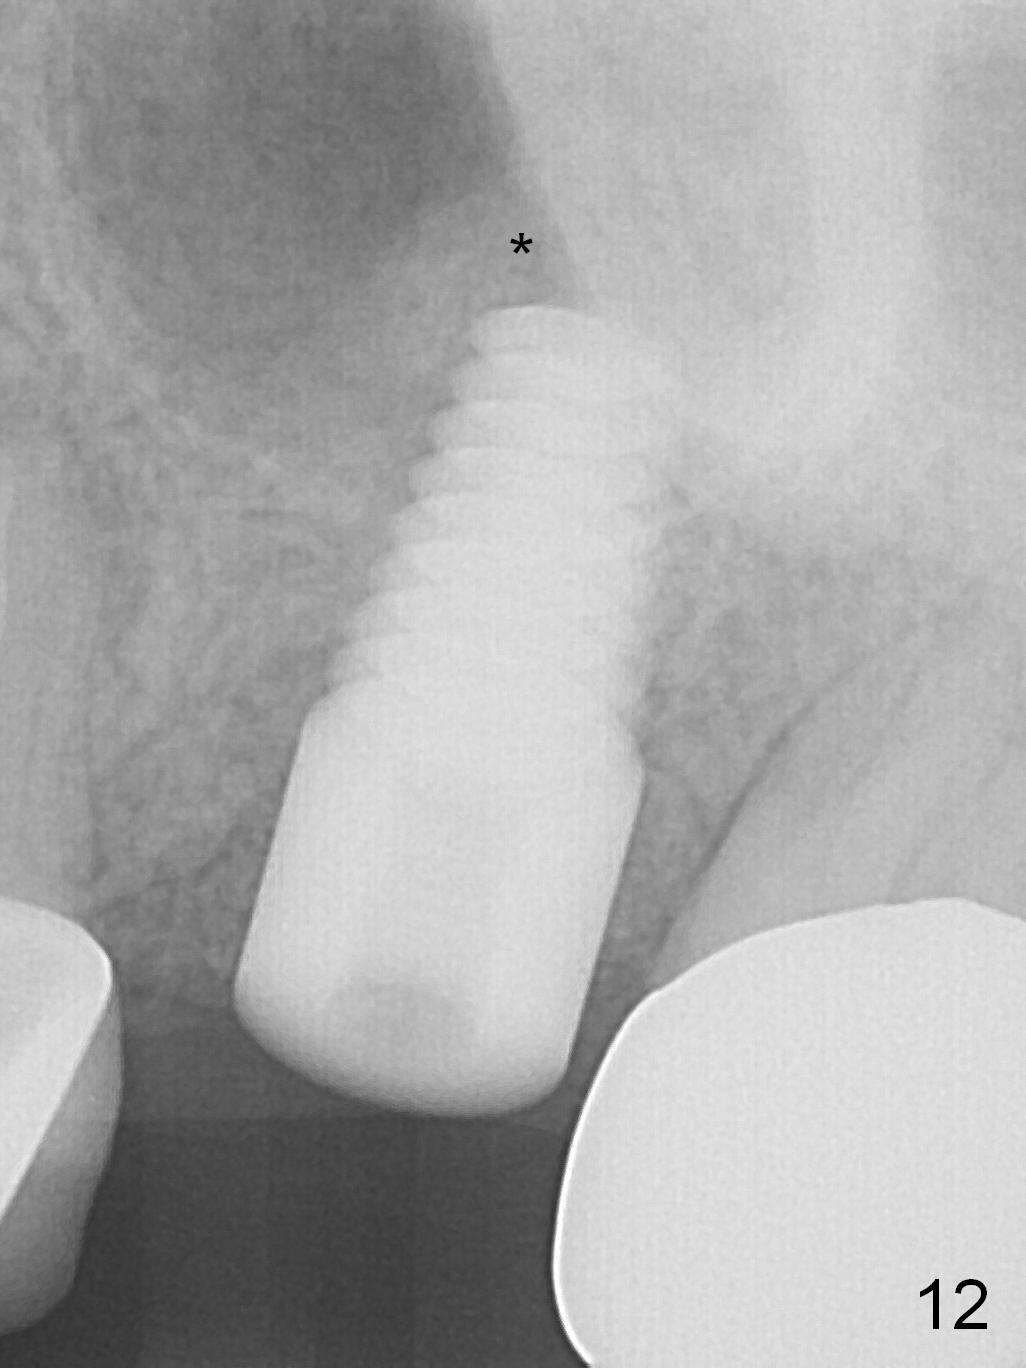

The patient is doing well 9 days postop. The immediate provisional is loose and over-sized. It is removed for trimming and reline; the socket and bone graft (Fig.8 *) are healing. It appears that an angled abutment is required next time of provisional revision. When an angled abutment is being placed 23 days postop (Fig.9), it appears to wiggle the implant due to its long leverage. Instead a healing abutment is placed. The implant is unstable 4.5 months postop with seemingly excessive bone-implant gap (Fig.10 <). The 5.5x9 mm implant is removed. A 5x17 mm tap is used to change the trajectory and sinus lift, followed by 6x17 one (Fig.11). Finally a 6x14 mm tissue-level implant is placed with insertion torque > 50 Ncm (Fig.12; vs. <20 Ncm (Fig.7,10)) and improved trajectory. An immediate provisional is fabricated to prevent the mesial drifting of the tooth #15 (Fig.13 P (*: occlusal clearance)). By using the taps and placing the longer implant, the sinus lift is more obvious (compare Fig.10 and 12 (*)). Sinus lift remains evident 3.5 months postop (Fig.14) with apparently osteointegration (Fig.15).